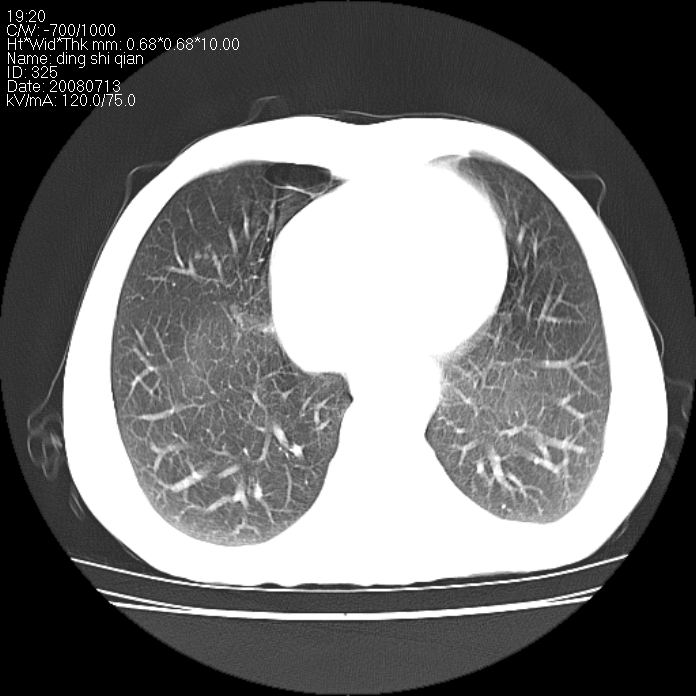

标题: CT14654:男 50岁 近来胸痛 [打印本页]

标题: CT14654:男 50岁 近来胸痛

右侧上肺块状软组织影,浅分叶,边缘毛刺证,与胸膜粘连,考虑:周围性肺癌

右肺上叶周围型肺癌可能性大。

右侧上肺块状软组织影,浅分叶,边缘毛刺证,与胸膜粘连,考虑:周围性肺癌!支持!

典型右肺周围型肺癌

右肺上叶周围型肺癌。